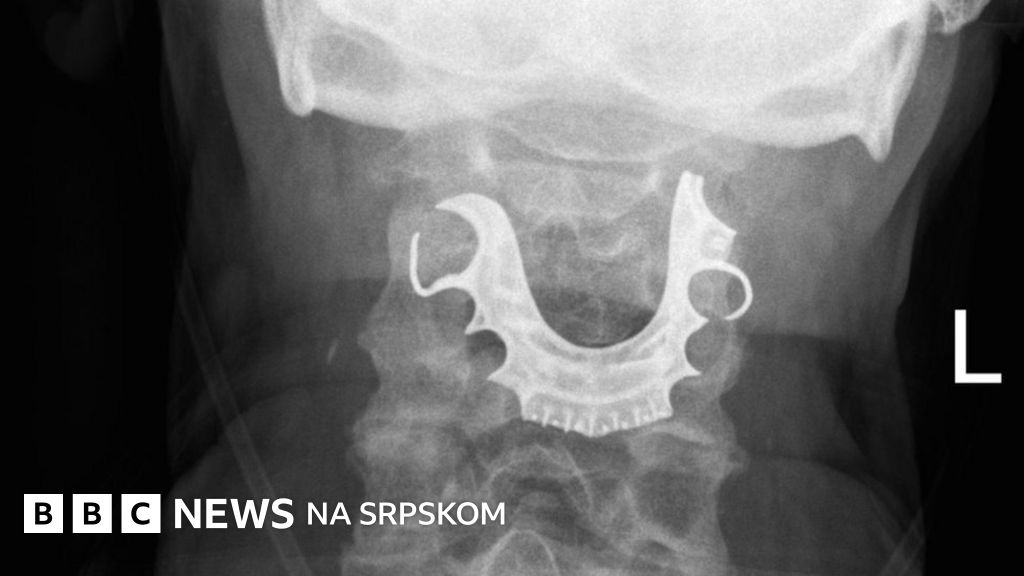

Tokom rutinske operacije u grlu pacijenta zaglavila se proteza i lekari nisu uspeli da je nađu osam dana.

Kada se muškarac dva dana kasnije ponovo javio kod lekara, medicinsko osoblje pregledalo je grlo i glasne žice - i pronašlo polukružni predmet koji leži preko njih.

On je lekarima rekao da je za vreme operacije u bolnici izgubio protezu.